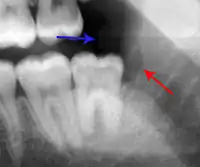

The periodontal ligament becomes inflamed and there may be pain when biting or tapping on the tooth. On an X-ray, bone resorption appears as a radiolucent area around the end of the root, although this does not manifest immediately.[10]: 228 Acute apical periodontitis is characterized by well-localized, spontaneous, persistent, moderate to severe pain.[6]: 125–135 The alveolar process may be tender to palpation over the roots. The tooth may be raised in the socket and feel more prominent than the adjacent teeth.[6]: 125–135

- Radiographs utilized to find dental caries and bone loss laterally or at the apex.

Decay (green) with apical abscess (blue)